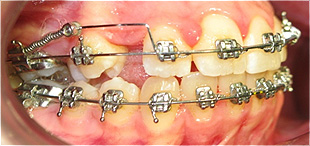

Dente canino não erupcionado e apinhamento dentário.

Criação de espaço para tração do dente canino, após 6 meses de tratamento.